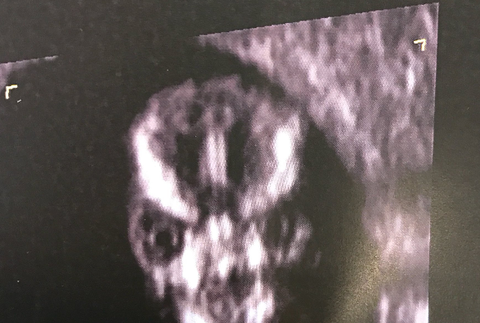

Mladá žena sa podobne ako stovky iných tehuliek pochválila na sociálnej sieti fotkou vytúženého potomka z ultrazvuku. Aj keď nie sú zábery zo sona bohvieakej kvality, Sharni neušlo, že jej bábätko vyzerá inak ako deti na podobných snímkach.

"Môj doktor si povedal, že mi urobí záber hlavičky dieťatka. Bola to tá najstrašidelnejšia vec, akú som kedy videla vo svojom živote," zverejnila Sharni na svojom Twitteri.

Internetoví trollovia si na jej príspevku okamžite zgustli. Fanúšikovia ságy Harry Potter sa zhodli v tom, že drobček je pravdepodobne potomkom zlého Voldemorta. Ostatným užívateľom zase pripomína postavy z filmov Predátor, Terminátor či Saw. Bábätko dostalo tiež prívlastky "diabol" alebo "čisté zlo".

Tehotnú ženu vydesil jej ultrazvuk